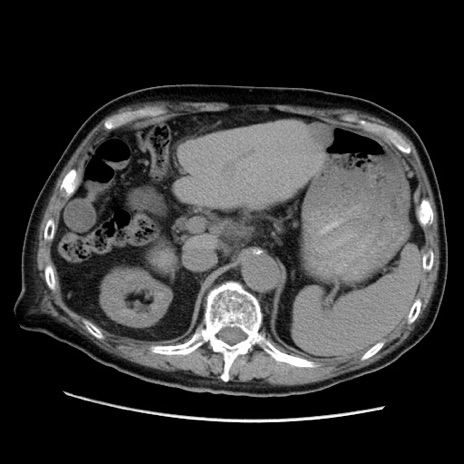

症例21(横断像)

【症例】70歳代男性

【主訴】腹痛

【現病歴】肝硬変・肝細胞癌にてかかりつけの方。約9時間前に食後より腹痛出現。症状が徐々に増悪し、嘔吐出現したため来院。

【既往歴】肝硬変、肝細胞癌(RFA、TACE後)

【身体所見】意識清明、表情苦悶様、BT 36℃、BP 129/78mmHg、P 88bpm、SpO2 97%(RA)、右上腹部から心窩部にかけて圧痛あり、反跳痛なし、筋性防御あり。

【データ】WBC 5800、CRP 0.16